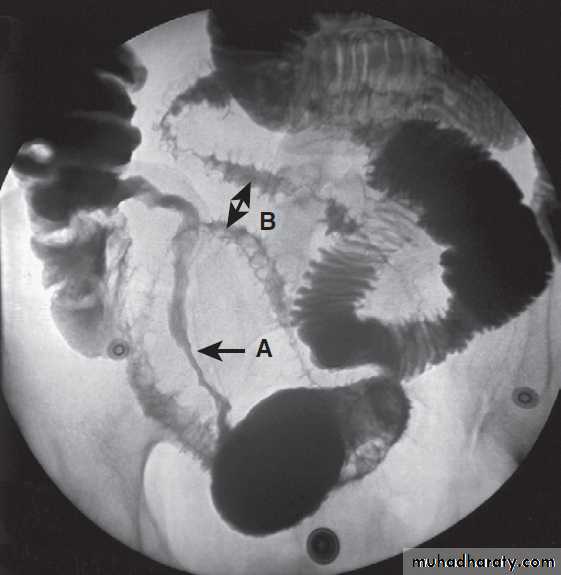

Contrast radiology in the investigation of gastrointestinal disease

A Non-ionic contrast swallow shows leakage of contrast (arrow) into the mediastinum following stricture dilatation. B Barium follow-through. There are multiple diverticula (arrows) in this patient with jejunal diverticulosis. C Barium enema showing severe diverticular disease. There is tortuosity and narrowing of the sigmoid colon with multiple diverticula (arrows).Imaging in gastroenterology :Examples of ultrasound, CT and MRI. A Ultrasound showing large gallstone (arrow) with acoustic shadowing. B Multidetector coronal CT showing large solid and cystic malignant tumour in the pancreatic tail (arrow). (PV = portal vein; L = liver) C Pelvic MRI showing large pelvic abscess (arrow) posterior to the rectum in a patient with Crohn’s disease. D Fused CT-PET image showing two liver metastases (arrows).